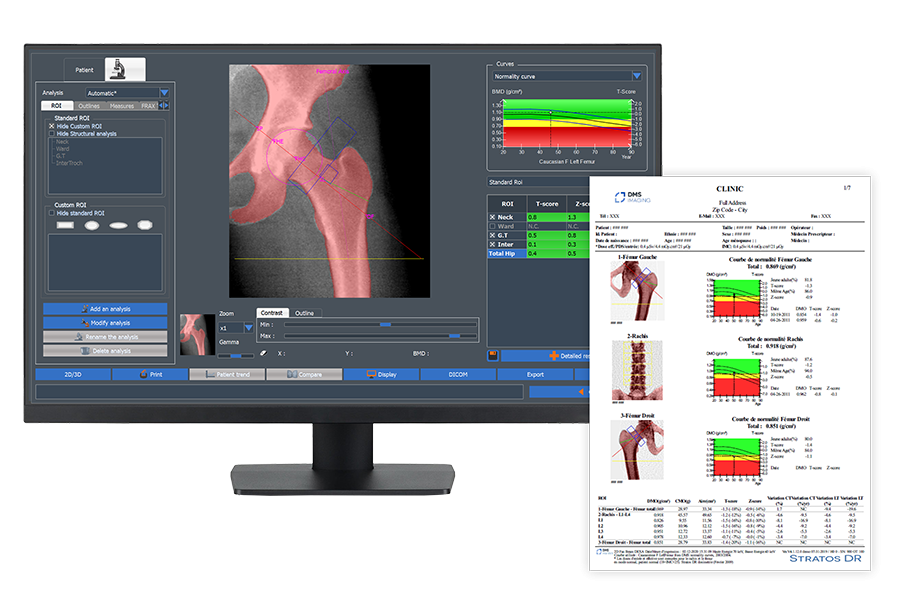

In-house intuitive software

Our software designed to assess bone health and body composition measures includes some key features with a seamless and intuitive workflow for great user experience.

– Advanced connectivity: Fully compatible with DICOM, ensuring secure and efficient integration with PACS system

– Optimal workflow: fast scan, patient repositioning, automatic analysis, easy sharing

– Automatic & personalised reports and letters to patients & physicians

– Patient progress tracking or follow-up over time with trend graphs and comparative analytics

– Multi-user access across different workstations for collaborative diagnostics

INNOVATIVE 3D-DXA TECHNOLOGY

3D-DXA is a breakthrough technology that transforms routine BMD images into 3D visualizations of the femur. It assesses separately both cortical and trabecular bone compartments for more accurate diagnosis and advanced risk assessments validated against QCT standards. Furthermore, it enhances clinical decision-making with sharper insights into bone microstructure for optimized treatment to patients.